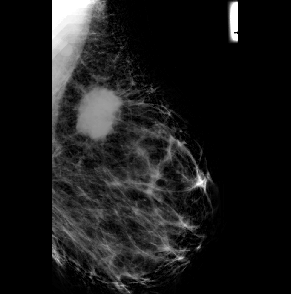

Filtering is a technique for removing unwanted information from an image by perception and making it more suitable for the next step in image processing. To remove speckle sounds from photos, various types of filtration are used. The image was de-specked using a mean-median filter in this investigation. The image before and after applying the mean-median filter is shown in Figure 2(b) and 2(b), respectively.

Figure 2. (a) Input image (b) denoised image after mean- median filter